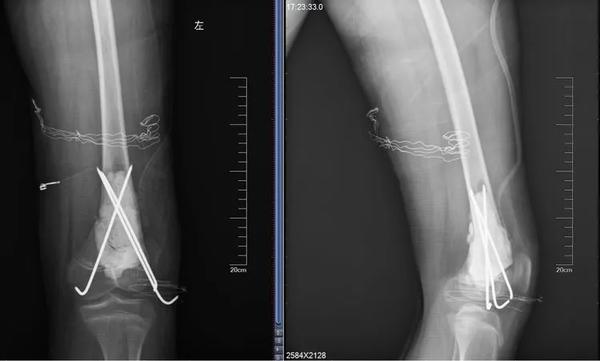

12歲的男孩兒浩浩,在學校上體育課,扭傷后突發(fā)右側大腿劇烈疼痛,不能活動,被家人緊急送到醫(yī)院,當?shù)蒯t(yī)院拍片后提示右股骨中下段斜行骨折。隨后,醫(yī)院按照一般骨折處理。

當?shù)蒯t(yī)生將病理組織送河南省腫瘤醫(yī)院病理會診,提示為骨肉瘤。消息猶如晴天霹靂,但更讓兩個孩子的父母痛苦的是,“由于按一般骨折做了手術、打了鋼板和鋼釘,破壞了腫瘤外面原本相對完整的包膜,這個自然屏障一旦被破壞,腫瘤細胞就會‘污染’周圍組織,以后想再切干凈就更困難了。”河南省腫瘤醫(yī)院骨與軟組織科主任、主任醫(yī)師姚偉濤表示。

身體異常:排除感冒、發(fā)燒引起的,患者出現(xiàn)持續(xù)發(fā)熱,并伴有體重下降,活動能力下降,且有難以解釋的持續(xù)性疼痛。骨折:腫瘤持續(xù)“破壞蠶食”骨質(zhì),最后就像浩浩和晨晨一樣,輕微的外力下就會發(fā)生一處甚至多處骨折。揪出骨肉瘤 核磁是關鍵那怎么才能確診骨肉瘤呢?檢查骨肉瘤首先要拍X片,其次是磁共振,最終要依靠活組織檢查來確診。一定不能忽視磁共振檢查。王鑫提醒道:骨肉瘤就像一個表面看起來很小的水坑,實際上坑里的水已經(jīng)向周圍浸潤了很大一片。在X光片上僅能看到很小的一個病灶,而在磁共振上,可以判斷腫瘤的實際大小和確切范圍,減少誤診漏診。就像浩浩、晨晨這樣,以為只是骨折,拍了片子,即使看出有一些異常,也可能沒在意,這樣打鋼板、鋼釘,弄破了瘤子后期治療就不好進行了。磁共振不僅對確診有幫助,而且對治療也有指導作用。“手術時要在腫瘤周圍正常組織內(nèi)切除腫瘤,保證腫瘤的邊界干凈,才能提高治愈效果。”王鑫解釋說。

最終,王鑫醫(yī)師組為浩浩、晨晨兩位小朋友選擇了新輔助化療,待疼痛癥狀緩解后,手術取出鋼板、鋼釘,并通過擴大切除手術,完整切除長瘤子部分的股骨,并進行體外滅活,搭配腫瘤型組配人工膝關節(jié)置換,達到了既完整切除腫瘤,又保全了孩子肢體功能的目的。做到這些讓孩子遠離骨肉瘤骨肉瘤的致病原因目前并不明確,常認為是多種因素綜合導致,比如放射性輻射、接觸化學物質(zhì)、基因突變等。首先,家長對于孩子出現(xiàn)身體異常,一定要引起重視,發(fā)現(xiàn)子女在不明確病因的情況下出現(xiàn)了骨頭疼痛、關節(jié)腫痛,請及時前往醫(yī)院查明病因;家長要多鼓勵孩子外出進行戶外運動,不要接觸過多放射性輻射;另外,戶外運動時,也要注意關節(jié)處的保護,提醒孩子注意運動秩序和方式,避免造成骨骼損傷及軟組織拉傷。王鑫提醒,如果出現(xiàn)問題,懷疑骨腫瘤性疾病,尤其是合并病理性骨折,家長一定要帶孩子到專業(yè)的骨腫瘤科就診,必要時行磁共振檢查,仔細甄別骨折原因!